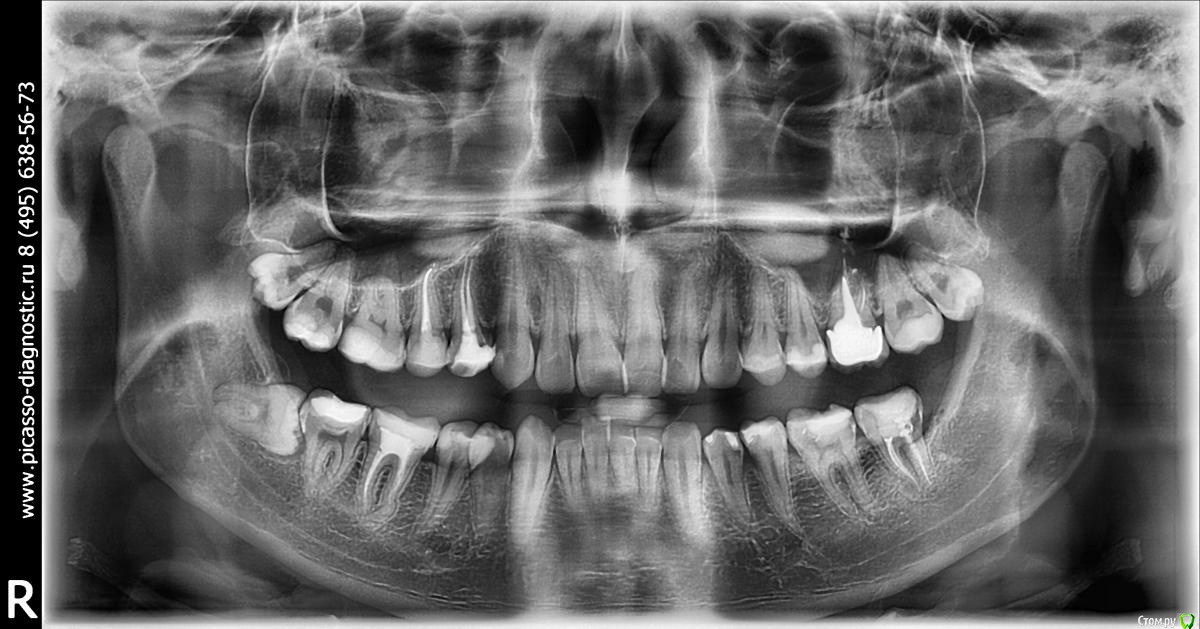

wasley711 Опубликовано 28 ноября, 2019 Поделиться Опубликовано 28 ноября, 2019 Добрый день. Нужно ли удалять нижнюю восьмерку? С соседней семеркой все нормально или нет?Жалоб нет. Большое спасибо! Ссылка на комментарий

wasley711 Опубликовано 28 ноября, 2019 Автор Поделиться Опубликовано 28 ноября, 2019 ОПТГ. Ссылка на комментарий

red_butler Опубликовано 28 ноября, 2019 Поделиться Опубликовано 28 ноября, 2019 Все три удалять 2 Ссылка на комментарий

wasley711 Опубликовано 6 декабря, 2019 Автор Поделиться Опубликовано 6 декабря, 2019 (изменено) Все три удалятьСпасибо!Нижний удалил, верхние потом. Изменено 6 декабря, 2019 пользователем wasley711 Ссылка на комментарий